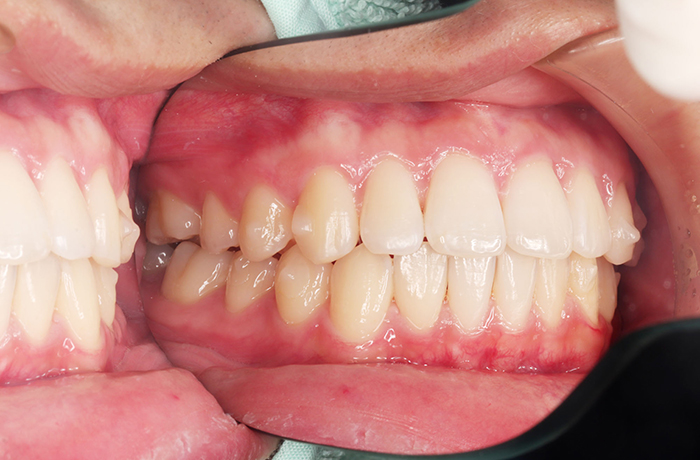

A様

治療前

before

年齢 31歳

性別 女性

治療名称 マウスピース型カスタムメイド矯正歯科装置(インビザライン)・コンプリヘンシブパッケージ(難症例)

総額治療費用 935,000円(税込10%) 金額備考 精密検査料・診断料 33,000円(税込10%)

治療期間 3年4か月 通院頻度など 1か月ごと(途中から3~4か月ごと)

患者の症状 叢生、正中のずれ、上顎左右側切歯の口蓋側転位(交叉咬合)

治療方法 非抜歯で、マウスピース型カスタムメイド矯正歯科装置(インビザライン)による矯正

歯列弓を拡大することで非抜歯を可能にしました。

治療結果 側切歯の交叉咬合は解消、上下正中のずれも改善し咬み合わせが良くなりました。